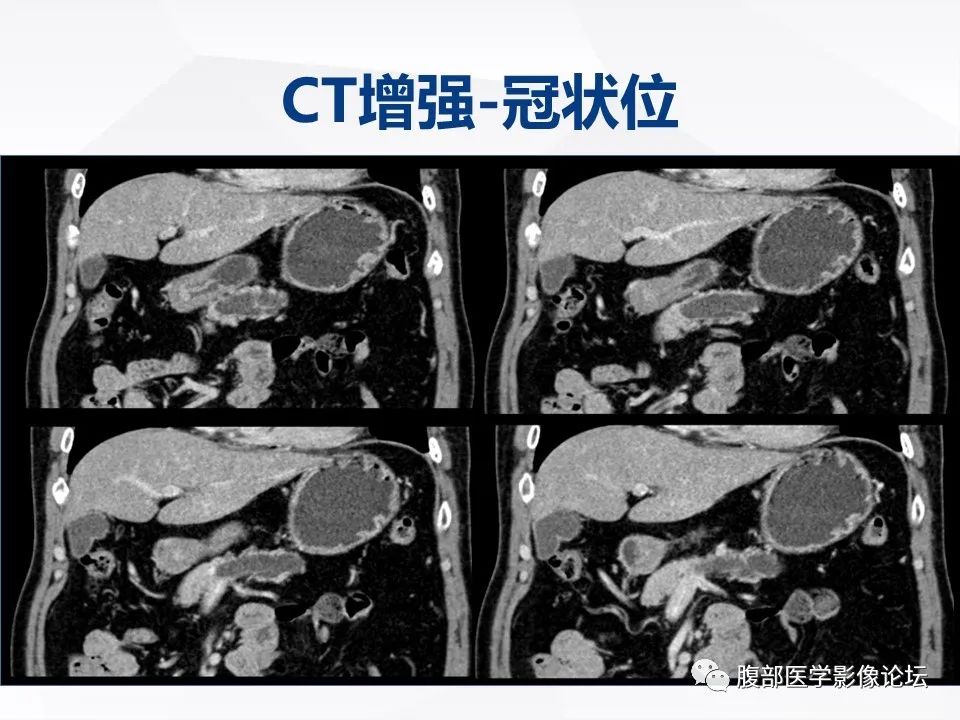

【病例】胰腺导管内神经内分泌肿瘤1例CT及MR-4